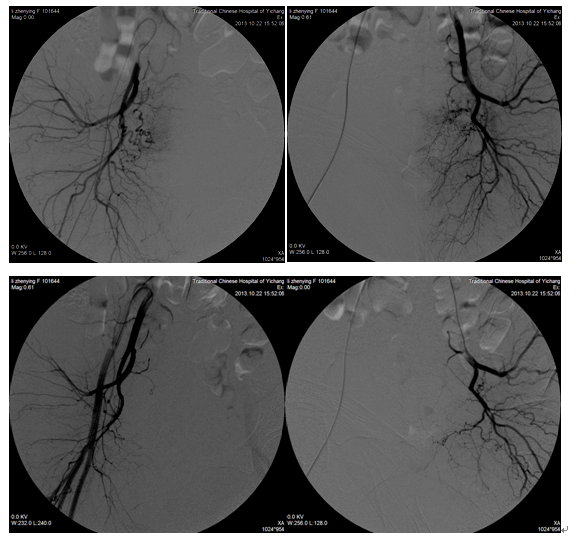

肺癌骨转移

典型病例一、男、87岁,2010年因肺癌右侧大腿转移剧烈疼痛,磁共振检查右下肢软组织肿块,行微创介入栓塞术后第二天患者疼痛消失。